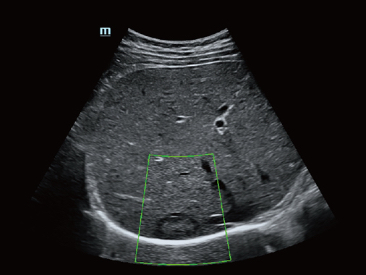

Sejak didirikan, Mindray terus mencari cara baru untuk meningkatkan keandalan diagnostik. Didukung Teknologi ZONE Sonography? terkini, platform ZST+ baru Resona 7 meningkatkan kualitas gambar ultrasound melalui pengambilan zona dan pemrosesan data saluran.

Selain kualitas gambar premium, Resona 7 juga meningkatkan kemampuan penelitian klinis dengan V Flow revolusioner untuk evaluasi hemodinamika vaskular, serta pengambilan penampang tercanggih dari rangkaian data 3D untuk diagnosis CNS pada janin. Kombinasi pengoperasian multisentuh berbasis gerakan yang paling intuitif dengan semua fitur klinis penting membuat Resona 7 menjadi gebrakan baru dalam inovasi ultrasound.